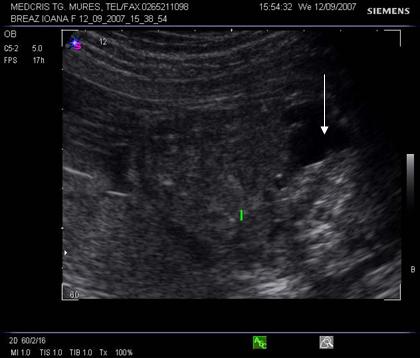

Fig. nr. 268. Formatiune anecogena abdominala fetala independenta de rinichi, la 28 sapt,ulterior in crestere la copilul de 3 ani

Fig. nr. 269. La peste 3 ani de la diagnosticul intrauterin, formatiunea tumorala abdominala ajunge la dimensiunea de 12 cm diametru si cu o structura inomogena cu mici hiperecogenitati sugestive ptr un teratom